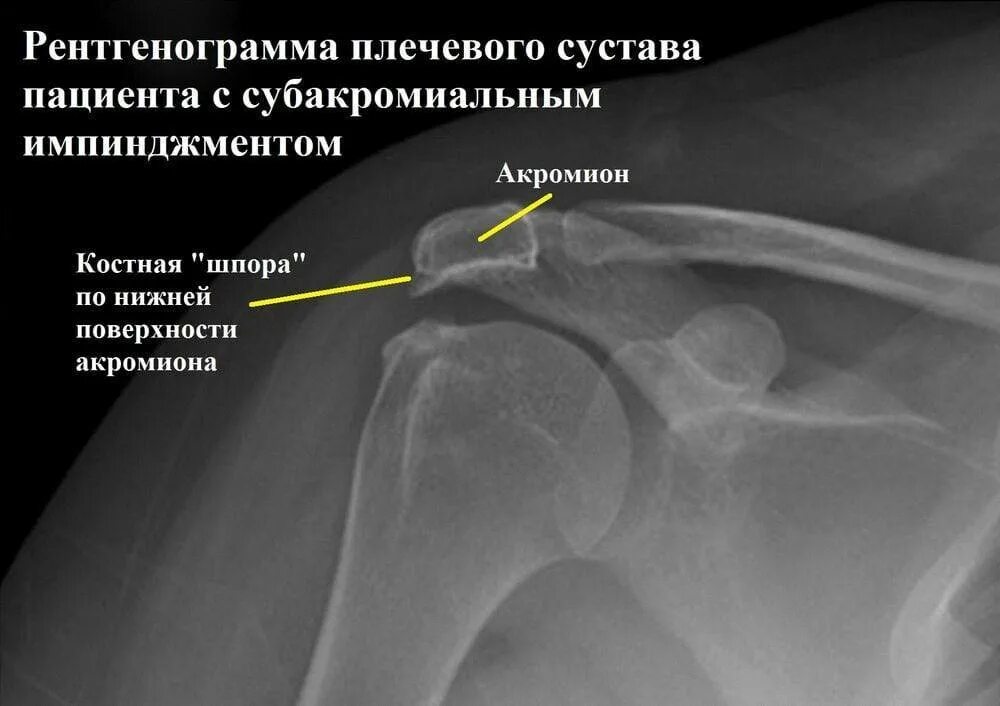

Синдром сдавления ротатора плеча